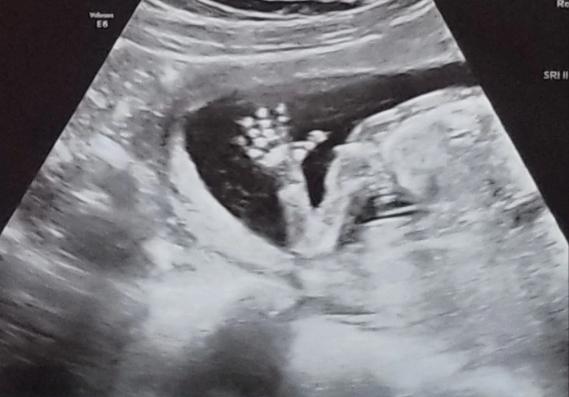

贝瑟尼在去做超声波检查时,医生怀疑她有双子宫,医生对此感到十分困惑,贝瑟尼称:“从未见过拥有和我一样解剖结构的人,医生也没什么可以告诉我的。”

然而,双子宫并不是她的第一个意外,在大约一个月后,她再次去做检查时,她的妇科医生发现她有着完整的阴道隔膜,将阴道分为两部分,这也就意味着她有两个阴道。贝瑟尼称:“以前从未听说过,这太不可思议啦,我甚至都不敢想象。”

“在怀孕九个月做产检的时候,我看到宝宝健康的心跳,我才感到希望。”